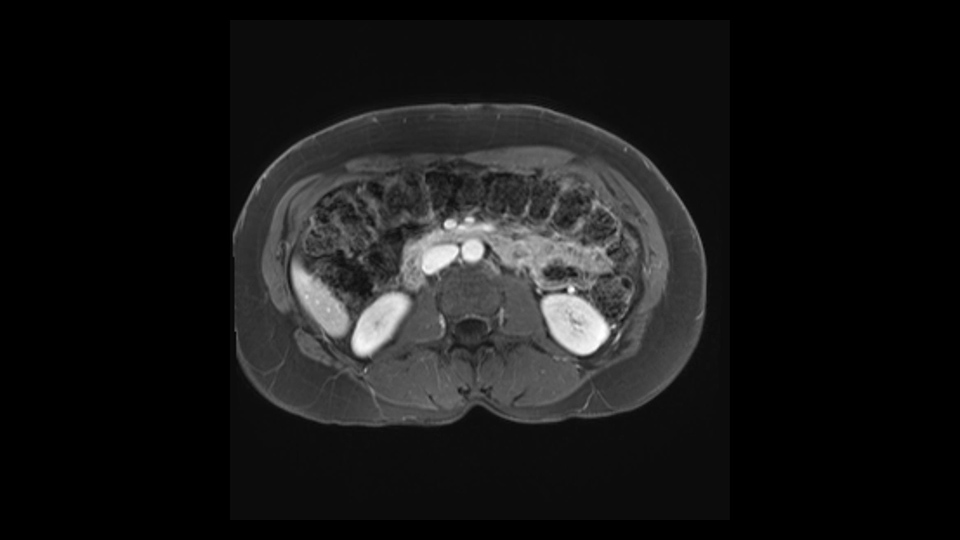

The slowing down moments or considerations that I give when I look at the scan and plan my distal pancreatectomy is how far away the tumor is to the portal vein and do I have to formally create a tunnel behind the pancreas on top of the portal vein or do I have to take the pancreas further to the left of the portal vein or the patient’s left of the portal vein. So here I can see that here is the tumor here. I can see that the tumor is a fair way away to the patient’s right and so I will likely not have to take or create the tunnel formally in this procedure. And that speaks a lot to the resection margins. So its important when you’re doing a distal pancreatectomy or any procedure potentially for oncologic reasons to get clearance of the tumor and to take the tumor kind of intact.

So first, I'll show you the scan. Here's the traditional view, where you see the cyst, which is in the body of the pancreas. And you see over here, it's got a quite thick wall. And going a little bit back also, here you see a septation which is very important, because I think a septation is what separates this from, for instance, the pseudocyst of the pancreatitis. And also the location of the cyst you see here, abutting the adrenal gland and going down a bit more, it's also quite close to a bowel loop. So when thinking about this cyst: female, the location in the body of the pancreas, thick wall, septation, and as you can read in history, it was basically asymptomatic, so no signs of pancreatitis. So, this probably all points towards a mucinous cystic neoplasm.

Key features that I look at the imaging are: first I look at the distance between the cyst and the portal vein SMV confluence. So there are guidelines for this, they call the Yonsei guidelines, to decide to do it laparoscopically or open and basically it says that if it’s a cancer, at least a centimeter away from the celiac trunk or the venous confluence. This is a cyst. So maybe you could stretch that a bit, but you don't want to get into trouble there. So for this cyst if you look at it, it's nicely away from the confluence.

So unfortunately I cannot show you a coronal view but you can see it easily on this scan, going down first you see the celiac trunk and you see here, quite a nice distance between the celiac trunk and the beginning of the mucinous cyst. And if you go up here and follow down the portal vein confluence you also see a nice distance there.

So what I would normally do in these patients, I would look at the abutment of any other organs, one, which is here, potentially the adrenal gland and two the small bowel. And two, look at the distance from the vessels which I would normally do in a coronal view. So you can easily measure the distance and third I look at the insertion of the inferior mesenteric vein. Now we can probably also see that on here. Although it's better on a CT scan and it's better on a coronal view, you want to know where the inferior mesenteric vein comes into either the splenic or the SMV, because that is typically a very important slow down moment when you mobilize the lower portion of the pancreas knowing where the inferior mesenteric vein comes in either the splenic vein or the SMV. So those are I think the three most important points for the CT scan.